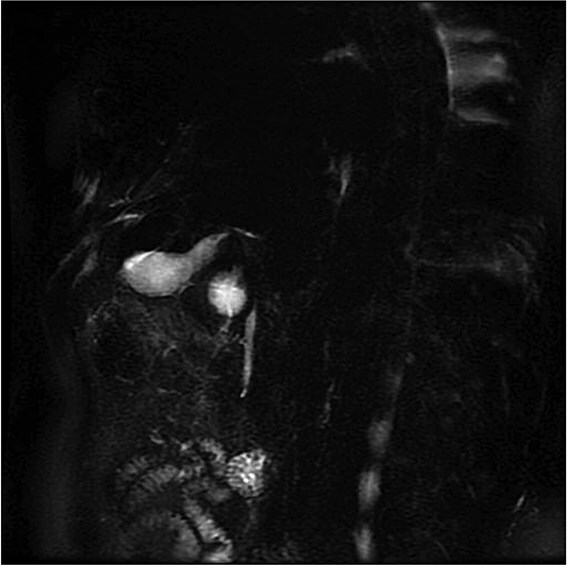

Gallbladder duplication is a rare congenital anomaly. Abnormal biliary anatomy is associated with an increased risk of complications, such as bile duct injury, during cholecystectomy. In this article, we present a clinical case of gallbladder duplication identified preoperatively by magnetic resonance cholangiopancreatography, which guided surgical planning. A 70-year-old man was admitted with acute cholecystitis, low-grade fever, jaundice, and dyspnea. Magnetic resonance cholangiopancreatography revealed a duplicated gallbladder (Type H). During surgery, the chronically inflamed upper gallbladder was completely resected. The larger lower gallbladder, with acute cholecystitis and a Mirizzi-like pattern, was partially resected due to severe inflammation and the inability to identify the cystic duct. The patient had an uneventful course. Gallbladder duplication is a rare congenital anomaly that may be associated with other congenital anomalies. Thorough preoperative imaging studies, meticulous surgical technique, and rigorous intraoperative monitoring are essential, as these abnormalities can lead to serious injuries.

Abstract Image